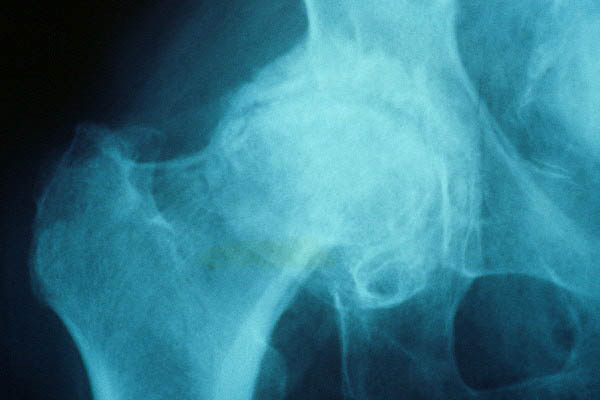

Fractura de cuello de fémur.

Artrosis avanzada de cadera. Anquilosis.

Artrosis anquilosante de cadera.

Atrosis avanzada de cadera.